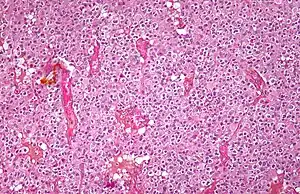

| Micrograph of an oligodendroglioma showing the characteristic branching, small, chicken wire-like blood vessels and fried egg-like cells, with clear cytoplasm and well-defined cell borders. H&E stain. | |

Oligodendrogliomas cannot currently be differentiated from other brain lesions solely by their clinical or radiographic appearance. As such, a brain biopsy is the only method of definitive diagnosis. Oligodendrogliomas recapitulate the appearance of the normal resident oligodendroglia of the brain. (Their name derives from the Greek roots 'oligo' meaning "few" and 'dendro' meaning "trees".) They are generally composed of cells with small to slightly enlarged round nuclei with dark, compact nuclei and a small amount of eosinophilic cytoplasm. They are often referred to as "fried egg" cells due to their histologic appearance. They appear as a monotonous population of mildly enlarged round cells infiltrating normal brain parenchyma and producing vague nodules. Although the tumor may appear to be vaguely circumscribed, it is by definition a diffusely infiltrating tumor.[6]

Classically they tend to have a vasculature of finely branching capillaries that may take on a "chicken wire" appearance. When invading grey matter structures such as cortex, the neoplastic oligodendrocytes tend to cluster around neurons exhibiting a phenomenon referred to as "perineuronal satellitosis". Oligodendrogliomas may invade preferentially around vessels or under the pial surface of the brain.[6]